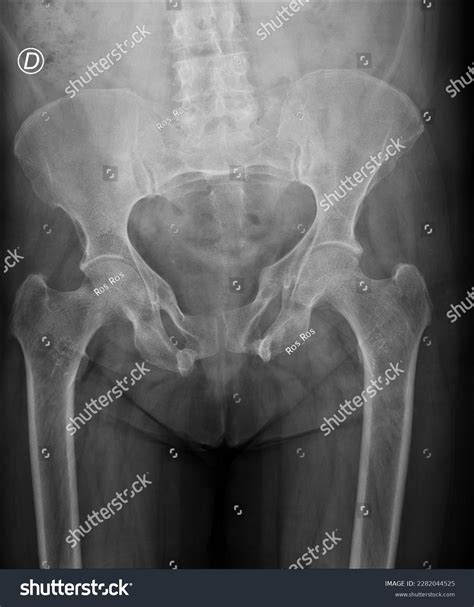

Diagnosing Pelvic Fractures

Diagnosing a pelvic fracture involves a combination of physical examination, medical history, and imaging tests. The diagnostic process typically includes:

• Imaging tests: X-rays, CT scans, and MRI scans may be used to visualize the bones and soft tissues of the pelvis, helping to confirm the diagnosis and determine the extent of the injury.